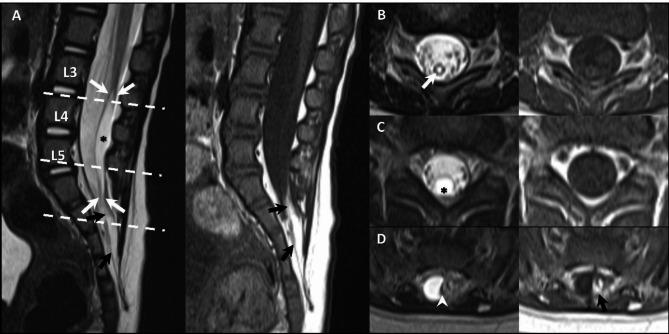

Retained medullary cord (RMC) is a recently defined term denoting closed spinal dysraphism arising from the failure of regression in secondary neurulation. Despite the acknowledgment of this condition, there needs to be more literature elucidating the radiologic manifestations of RMC. This study aimed to describe the MR imaging findings of RMC. A retrospective analysis was conducted on spinal MRI scans of pediatric patients with surgically confirmed RMC, from January 2014 to August 2023. The investigation focused on evaluating the following image characteristics: level and morphology of the cord-like structure (C-LS), the signal intensity in the far distal C-LS, nerve root-like structures originating from the C-LS, intradural fatty lesions, and arachnoid cysts. This study included 38 patients (19 girls, mean age 7.3 months) who showed a low-lying cord in all cases. The morphology of C-LS was either smooth tapered (50%) or hourglass with fusiform cystic dilatation (50%). The C-LS exhibited aberrant T2 hypointense signal compared to the juxta-proximal level. T2 hypointense signal vestigial nerves emanating from the C-LS and intradural fatty masses were observed (89.5%). Sacral arachnoid cysts in extradural location were identified in eight patients. The characteristic MR features of RMC revealed an extremely low-lying distal C-LS with smooth tapering or hourglass-shaped cystic dilatation of the caudal part, accompanied by an intradural fatty stalk and the aberrant signal vestigial nerve. This study suggests those radiologic findings can be RMC instead of the previously called terminal syrinx with low-lying conus.

脊髓残留(RMC)是一个最近定义的术语,用于表示源自二次神经发生中退化失败的闭合性脊髓脊膜裂。尽管已经认识到这种情况,但需要更多的文献来阐明 RMC 的放射学表现。本研究旨在描述 RMC 的磁共振成像(MRI)表现。对 2014 年 1 月至 2023 年 8 月期间经手术证实为 RMC 的儿科患者的脊髓 MRI 扫描进行了回顾性分析。研究重点评估了以下图像特征:索状结构(C-LS)的水平和形态、远段 C-LS 的信号强度、起源于 C-LS 的神经根样结构、硬脊膜内脂肪病变和蛛网膜囊肿。本研究纳入了 38 例患者(19 名女孩,平均年龄 7.3 个月),所有患者均显示低位脊髓。C-LS 的形态要么是平滑锥形(50%),要么是沙漏形伴梭形囊性扩张(50%)。C-LS 的 T2 低信号强度与近段相比异常。观察到源自 C-LS 的 T2 低信号强度的遗迹神经和硬脊膜内脂肪肿块(89.5%)。8 例患者在硬膜外部位发现骶部蛛网膜囊肿。RMC 的特征性 MRI 特征显示极低位置的远端 C-LS,其尾部呈平滑锥形或沙漏形囊性扩张,伴有硬脊膜内脂肪干和异常信号遗迹神经。本研究表明,这些放射学发现可能是 RMC,而不是以前称为低位圆锥的终末脊髓空洞症。